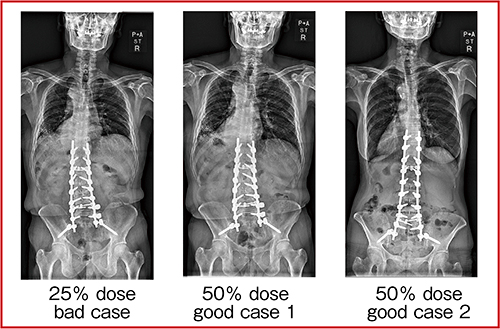

CXDIシリーズで使用可能な“アドバンスエッジ強調”は,ワンクリックで目的に応じた強調画像を作成する機能である。アドバンスエッジ強調を用いた全脊椎側面撮影では,従来画像処理の利用における撮影線量に対して,半分の撮影線量で臨床使用可能であることを示唆した報告もある2)。50%線量の全脊椎正面および側面の画像を示す(図3,4)。アドバンスエッジ強調を使用し,撮影条件の最適化を行ったところ,被ばく線量を50%低減でき,正面は0.23mGy,側面は0.66mGyで撮影可能であった。「日本の診断参考レベル(2020版)」(Japan DRLs 2020)のDRL値は,腰椎正面が3.5mGy,側面が9mGyであることからも,非常に低線量であると言える。

図3 50%線量の全脊椎正面像2)